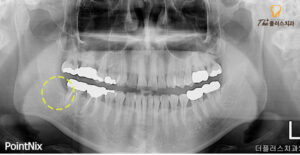

파노라마 사진을 보시면

신경관과 사랑니가 맞물려 있는 모습을

보실 수 있는데 이런 경우

안정적인 진행을 위해 CT를 촬영하여

사랑니의 정확한 맹출 방향과 치근의 휨 정도,

신경과 중첩된 모양 모두 정밀히 파악하여

발치를 진행해야 합니다.